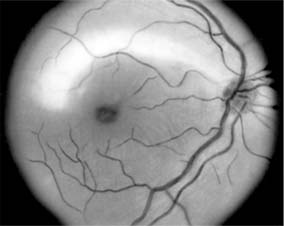

For papilledema to occur, the subarachnoid spaces around the optic nerve must be patent and connect the retrolaminar optic nerve through the bony optic canal to the intracranial subarachnoid space, thus allowing increased intracranial pressure to be transmitted to the retrolaminar optic nerve. There slow and fast axonal transport is blocked, and axonal distention, particularly noticeable at the superior and inferior poles of the optic disk, occurs as the first sign of papilledema. Hyperemia of the disk, dilated surface capillary telangiectases, blurring of the peripapillary disk margin, and loss of spontaneous venous pulsations are the signs of mild papilledema. Edema around the disk can cause a decreased sensitivity to small isopters on visual field testing, but circumferential retinal folds with changes in the internal limiting membrane reflexes (Paton's lines) will eventually become evident as the retina is pushed away from the choked disk; when the retina is pushed away, the blind spot will be enlarged to large isopters on visual field testing as well. In acute papilledema, probably as a consequence either of markedly elevated or rapidly increasing intracranial pressure, there are hemorrhages and cotton-wool spots, indicating vascular and axonal decompensation with the attendant risk of acute optic nerve damage and visual field defects (Figure 14-14). There may also be peripapillary edema (which can extend to the macula) and choroidal folds. In chronic papilledema (new window  Figure 14-15), which is likely to be the consequence of prolonged moderately raised intracranial pressure, a process of compensation appears to limit the optic disk changes such that there are few if any hemorrhages or cotton-wool spots. With persistent raised intracranial pressure, the hyperemic elevated disk gradually becomes gray-white as a result of astrocytic gliosis and neural atrophy with secondary constriction of retinal blood vessels, thus leading to the stage of atrophic papilledema (Figure 14-16). There may also be retinochoroidal collaterals (previously known as opticociliary shunts) linking the central retinal vein and the peripapillary choroidal veins, which develop when the retinal venous circulation is obstructed in the prelaminar region of the optic nerve. (Other causes of retinochoroidal collaterals are central retinal vein occlusion, optic nerve sheath meningioma, optic nerve glioma, and optic nerve head drusen.) Vintage papilledema is characterized by the presence of drusen-like deposits within the swollen optic nerve head.

Figure 14-16

Figure 14-16: Atrophic papilledema in a child with a cerebellar medulloblastoma. The disk is pale and slightly elevated and has blurred margins. The white areas surrounding the macula are reflected light from the vitreoretinal interface. The inferior temporal nerve fiber bundles are partially atrophic (arrows).